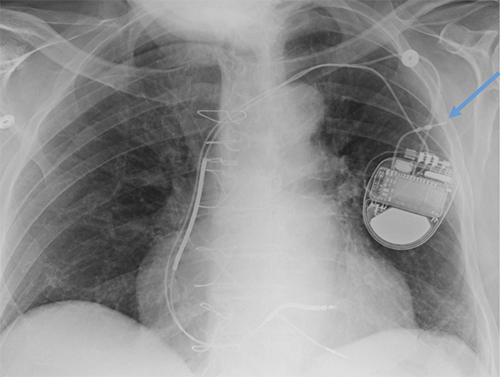

- CEID images with lead types:

Pacemaker with transvenous leads

Pacemaker with epicardial leads

Defibrillator lead

Subcutaneous defibrillator

Cut epicardial wires (often hard to see)

Abandoned leads

Abanded leads plus generator

Temporary transvenous lead

Leadless pacemaker

Abandoned, in situ intracardiac and epicardial leads